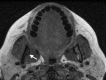

Medication-related osteonecrosis of the jaw (MRONJ) is a rare, severe debilitating condition from unknown causes. It is characterized by nonhealing exposed bone in a patient with a history of antiresorptive or antiangiogenic agents in the absence of radiation exposure to the head and neck region. The first case of MRONJ was reported in the early 2000s. Diagnostic criteria for MRONJ was developed by the American Association of Oral and Maxillofacial Surgeons (AAOMS) based on pharmacological history as well as clinical and radiographic features. Antiresorptive medications such as bisphosphonate and denosumab are currently considered the treatment of choice in patients with osteoclastic bone disease. These reduce bone turnover and improve bone density, thereby improving bone quality. These agents have also been shown to reduce the risk of osteoporotic fractures due to their potent effect in suppressing osteoclastic activity by slowing the remodeling process and increasing bone density, thereby improving quality of life for most of the patients. Despite the great benefits of bisphosphonates and other antiresorptive medications, osteonecrosis of the jaw (ONJ) due to the effects of these medications in the presence of a local risk factor is a significant drawback. Moreover, antiangiogenic drugs play a major role in developing bone necrosis. They are prescribed in cancer cases to prevent metastasis through the blood and lymph nodes. These drugs interfere with the formation of new blood vessels, resulting in ischemia and eventually ONJ. This risk can be managed by evaluating the route and the duration of administration as such a risk can be considered dose-time dependent. As a preventive measure, dental screening before initiating any type of ONJ-related medications can significantly lower the risk of ONJ. Treatment goals can be achieved through pain and infection control, in addition to the management of bone necrosis and resorption. The aim of this review is to identify all causative agents and summarize the preventive measures, diagnostic criteria, and treatment strategies related to MRONJ.

Figures